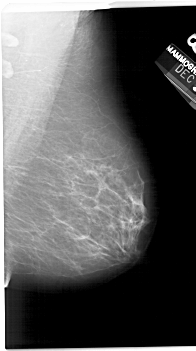

A_1245_1.LEFT_CC

LEFT_CC LINES 6856 PIXELS_PER_LINE 3811 BITS_PER_PIXEL 12 RESOLUTION 43.5 OVERLAY